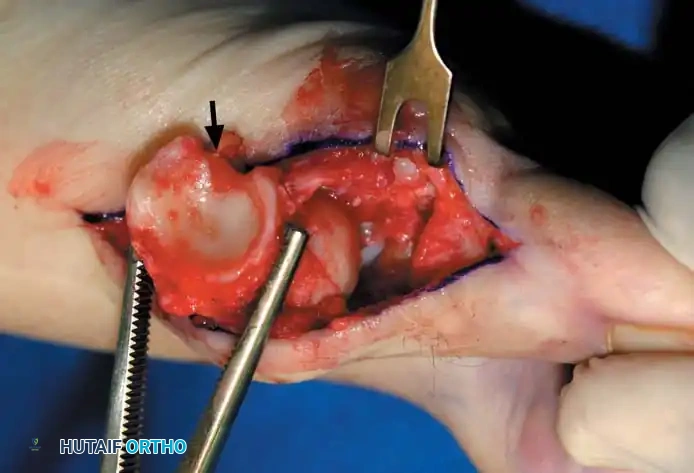

FIBULAR (LATERAL) SESAMOIDECTOMY: DORSAL APPROACH

• If after complete adductor hallucis release and preferably after a lateral capsular release, a fi bular sesamoidectomy is needed to correct the valgus deformity of the great toe fully, it should be done at this time.

• Adequately separate the fi rst and second metatarsal heads for exposure.

• Plantar fl ex the metatarsophalangeal joint 10 to 20 degrees, which reduces tension on the sesamoids.

• Grasp the fi bular sesamoid with a small Kocher clamp or sturdy tissue forceps, and pull it laterally into the intermetatarsal space (Fig. 78-20).

• Release the intersesamoid ligament. When this ligament has been incised, bring the fi bular sesamoid into the intermetatarsal space, where its removal is straightforward. Care must be taken when incising the intersesamoid ligament to avoid severing the fl exor hallucis longus tendon immediately plantar to it. If the tendon is severed, it probably should not be repaired at this level; loss of the tendon causes little if any functional impairment, and

REMOVAL OF THE FIBULAR SESAMOID

• When the medial eminence and phalangeal base have been excised, remove the fi bular sesamoid.

• Place a sturdy two-toothed retractor beneath the metatarsal head, and have an assistant lift it dorsally.

• Using a Freer elevator or a small osteotome for its strength, mobilize the fi bular sesamoid (Fig. 78-31A to C). This may be diffi cult in elderly patients with signifi cant deformity and adherence of the sesamoid to the metatarsal head. Lift the metatarsal dorsally for exposure (Fig. 78-31D and E).

• When the sesamoid is mobile, identify the fl exor hallucis longus tendon by placing traction on the hallux and fl exing and extending the interphalangeal joint of the hallux. The tendon is visible just distal to and in alignment with the sesamoids, which straddle it.

• Identify and expose the lateral neurovascular bundle just lateral to the tendon by blunt dissection.

• Pull the plantar medial capsule medially. This requires a fi rm grasp on the capsule. The medial traction brings the intersesamoid “ligament” into better view.

• Incise the intersesamoid ligament longitudinally with a No. 67 Beaver or No. 15 Bard-Parker blade. If tenotomy scissors are used, place one arm of the scissors under the ligament (this arm rests on the dorsal side of the fl exor hallucis longus) and the other arm dorsal to the ligament.

• When the intersesamoid ligament is incised, grasp the sesamoid fi rmly with forceps or a small Kocher clamp, fl ex the toe at the interphalangeal and metatarsophalangeal joints to relax the fl exor hallucis longus tendon, and pull the fi bular sesamoid distally and medially.

• With release of the intersesamoid ligament, the medial surface of the fi bular sesamoid is free from soft tissue. Distally, the sesamoid is free because of resection of the base of the proximal phalanx. This leaves two sides of the sesamoid, distal and medial, free of soft tissue.

• While pulling the sesamoid distally and medially, use a small blade to incise along the lateral margin of the sesamoid under direct vision. Keep pulling the head of the metatarsal dorsally and holding the hallux distracted and in fl exion. This greatly aids in identifi cation of the margins of the fi bular sesamoid, particularly laterally and proximally.

• The most diffi cult part of the sesamoidectomy and that which should be done last is release of the proximal lateral corner of the sesamoid where the fl exor hallucis brevis lateral head inserts. While incising the lateral capsular attachments to the sesamoid, do not bury the blade of the knife because the neurovascular bundle to the lateral side of the hallux is just lateral to the capsule.

• Now all attachments to the fi bular sesamoid have been removed except the lateral head of the fl exor hallucis brevis, which inserts on the proximal lateral margin of the sesamoid. This is a diffi cult section to remove; however, this section can be released under direct vision by pulling the sesamoid distally and medially and lifting the metatarsal head dorsally with a strong two-toothed retractor.

Fig. 78-31 Excision of fi bular sesamoid in modifi ed Keller procedure. With base of proximal phalanx removed and medial eminence excision, exposure of fi bular sesamoid is not as diffi cult from medial incision. A, Operative photograph showing elevation of fi rst metatarsal with strong two-tooth retractor and use of small osteotome to mobilize fi bular sesamoid and lateral capsuloligamentous (frequently contracted) structures. Osteotome is between metatarsal head and lateral sesamoid. When mobilization of fi bular sesamoid is complete, entire sesamoid is visible for excision. Note chondromalacia of tibial sesamoid articular surface medial to osteotome. B, Fibular sesamoid has been excised, and lateral capsular structures and conjoined tendon (in forceps) have been released. Neurovascular bundle to lateral side of hallux is adjacent to these structures. C, Diagrammatic representation of modifi ed Keller procedure. By excising fi bular sesamoid, valgus moment of conjoined tendon of fl exor hallucis brevis and adductor hallucis no longer pulls fl exor hallucis longus tendon laterally (carrying hallux with it) through capsulosesamoid plantar plate and pulley system. D, Metatarsal head must be lifted dorsally to excise fi bular sesamoid under direct vision. E, Note exposure of fi bular sesamoid after mobilization of metatarsal head. Continued